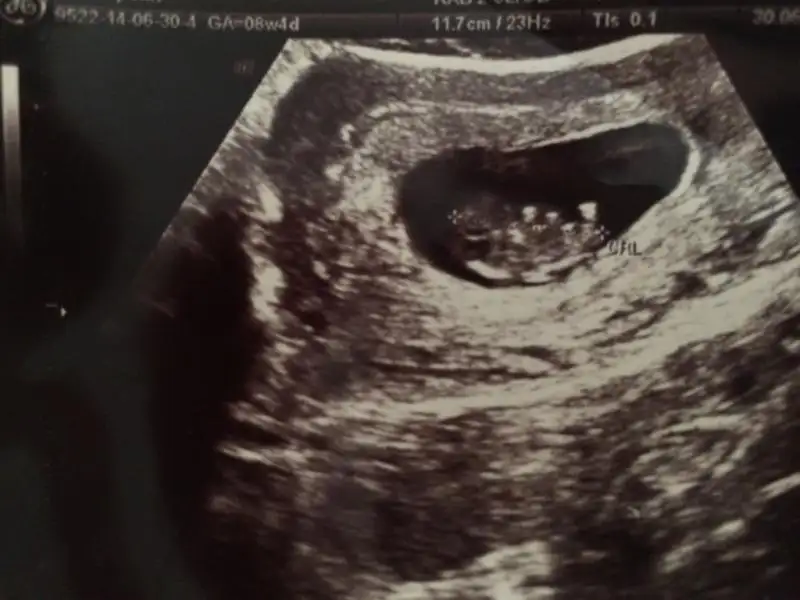

kızlar bakın bu da benim usg görüntüm

6+3 iken olan ultrason bu. Hep kiz cikardi ilk kez erkek olarak bir belirti olunca sasirdim :)

bu ne kızzzzzzz

ultrasonda böyle bişey mi çıkıyo

etrafındaki boşluk nee